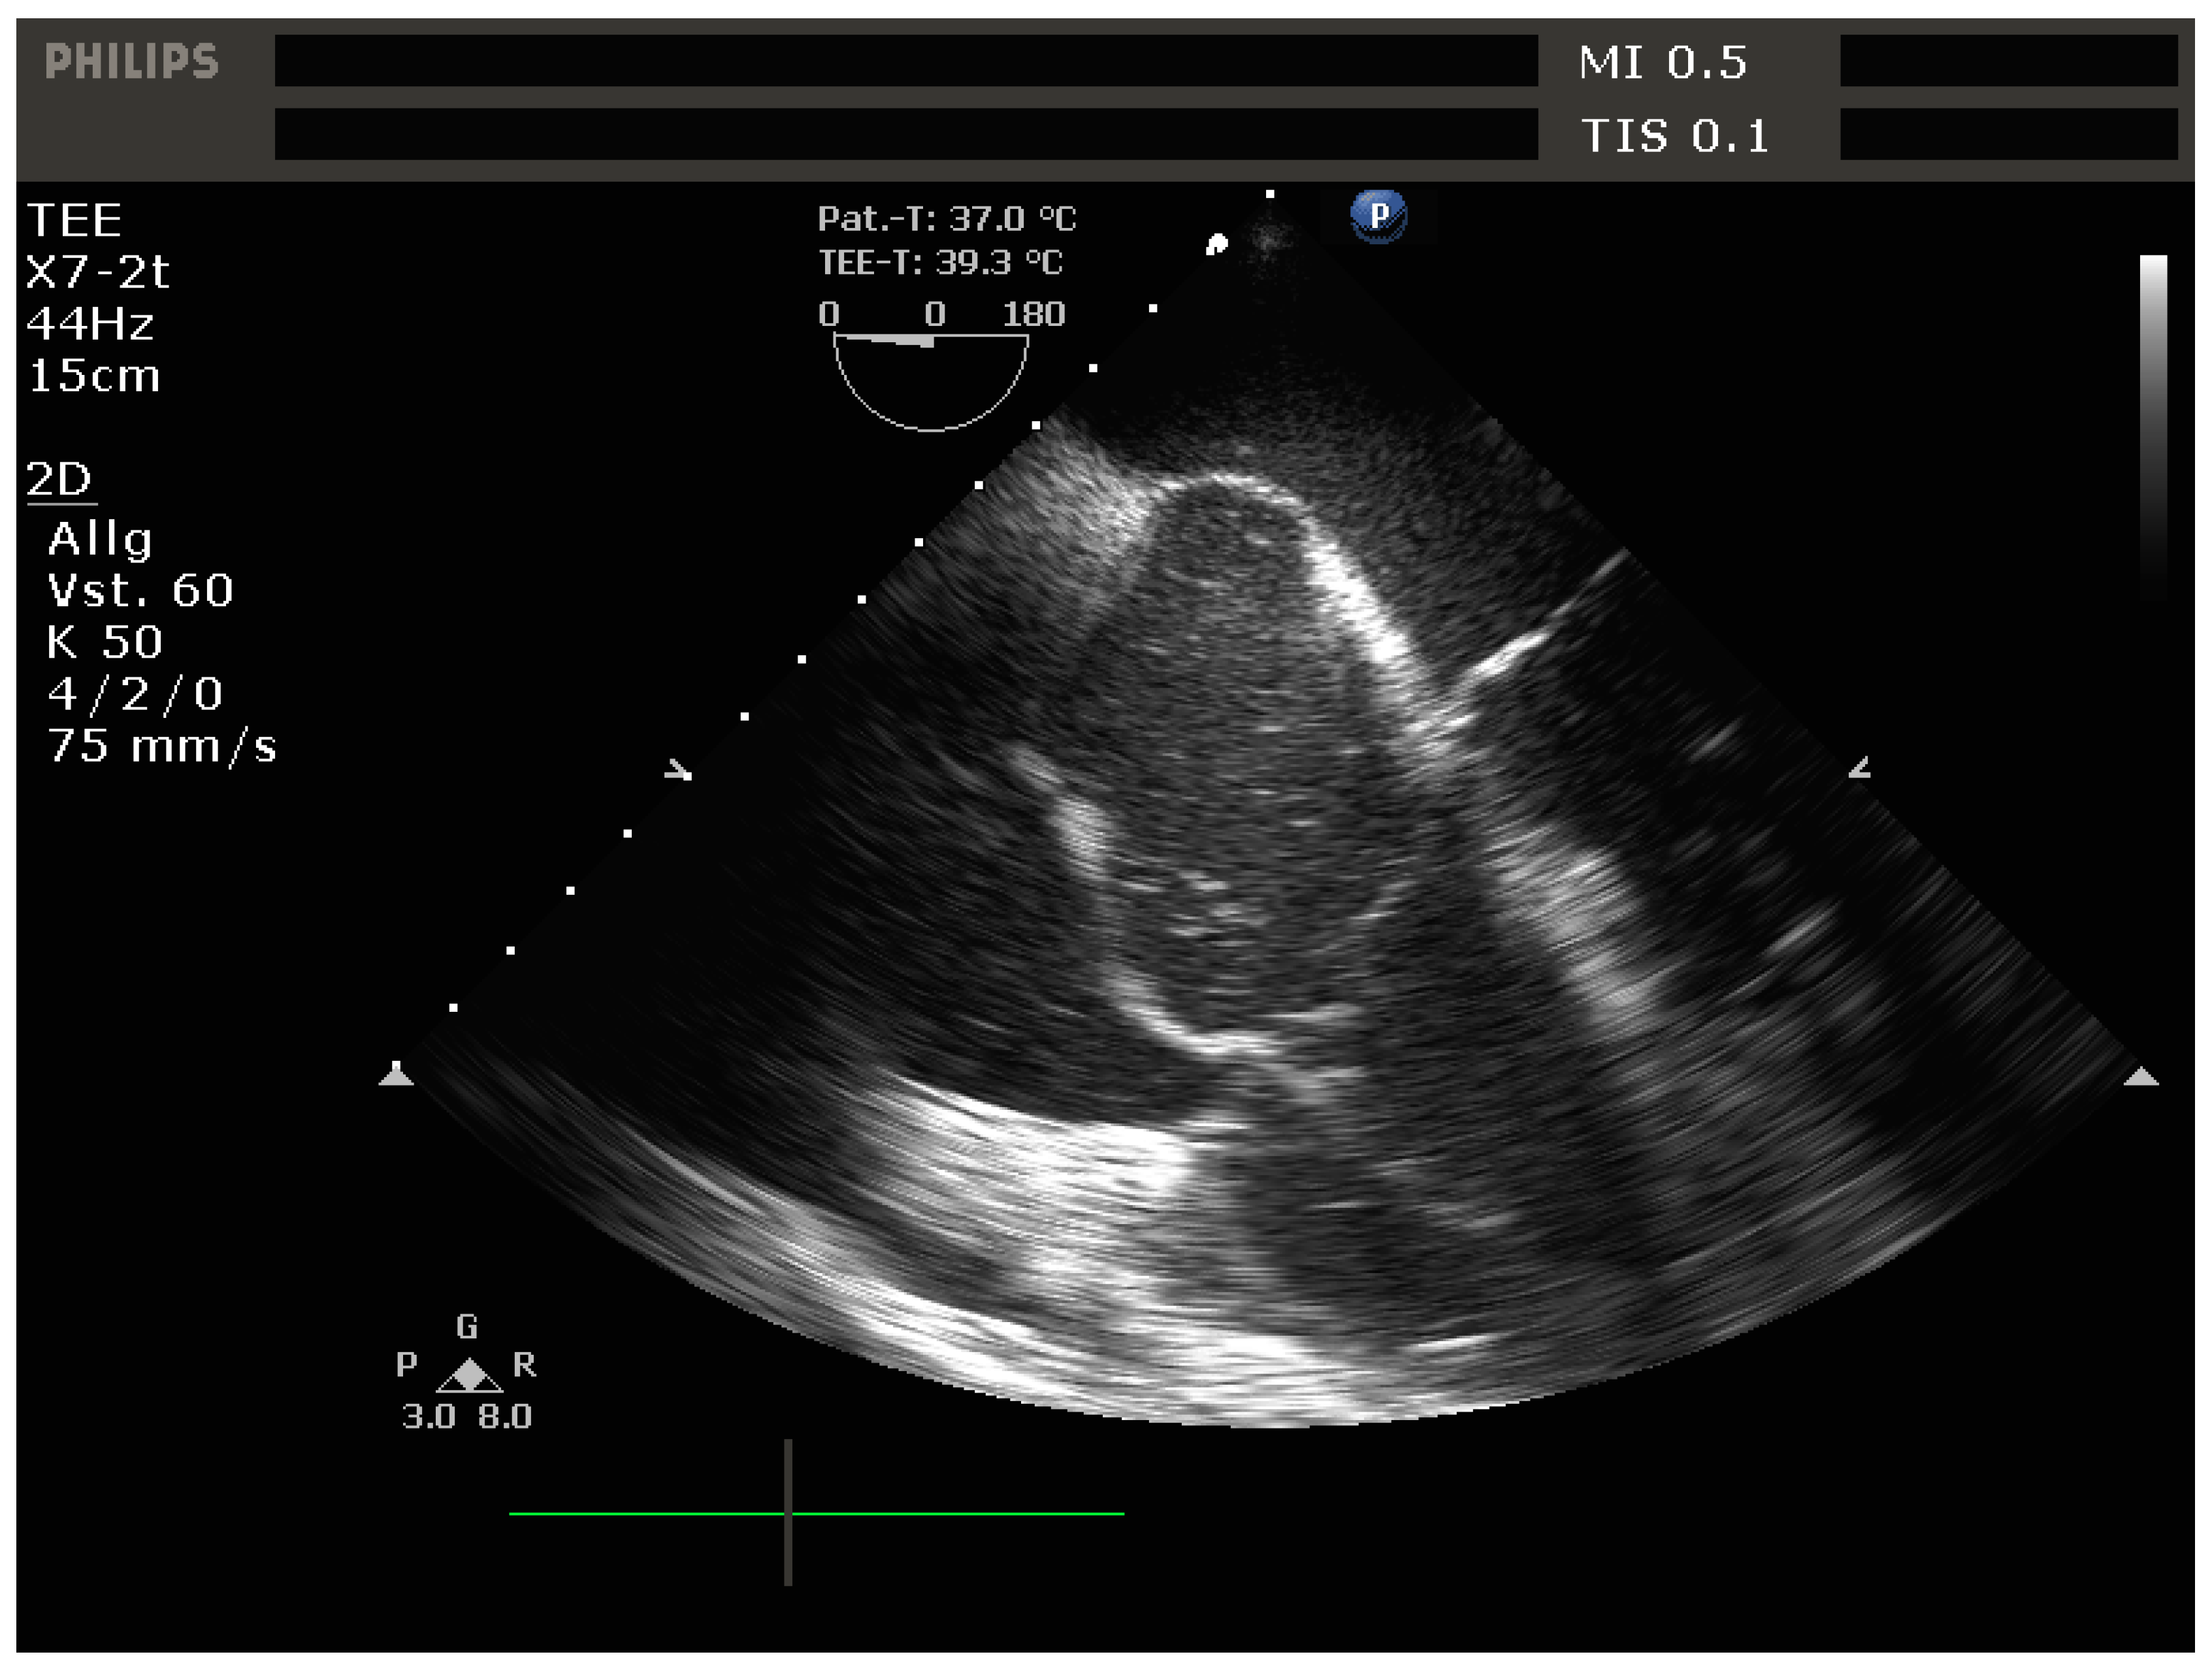

4.2.2. Echocardiography

- -

- Signs of RV dilation: D-shaping, increased RV:LV ratio, tricuspid regurgitation

- -

- Signs of impaired RV systolic function: reduced tricuspid annular plane systolic excursion (TAPSE)

- -

- Signs of elevated RV preload (plethoric inferior vena cava [IVC])